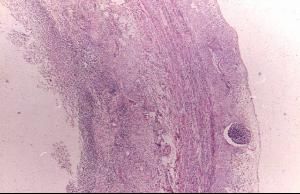

疾病名稱 疾病別名 疾病概述 疾病分類 疾病描述,包括淺表潰瘍,水腫,易碎和微小膿腫的病變則局限於結腸黏膜,雖然克羅恩病以迴腸末端和結腸受累為主,但病變可見於整個胃腸道,此病變常為潰瘍性,呈小塊狀...;病變局限於結腸時,組織學表現將有利於鑑別診斷。(1)症狀:主要症狀是糞便...